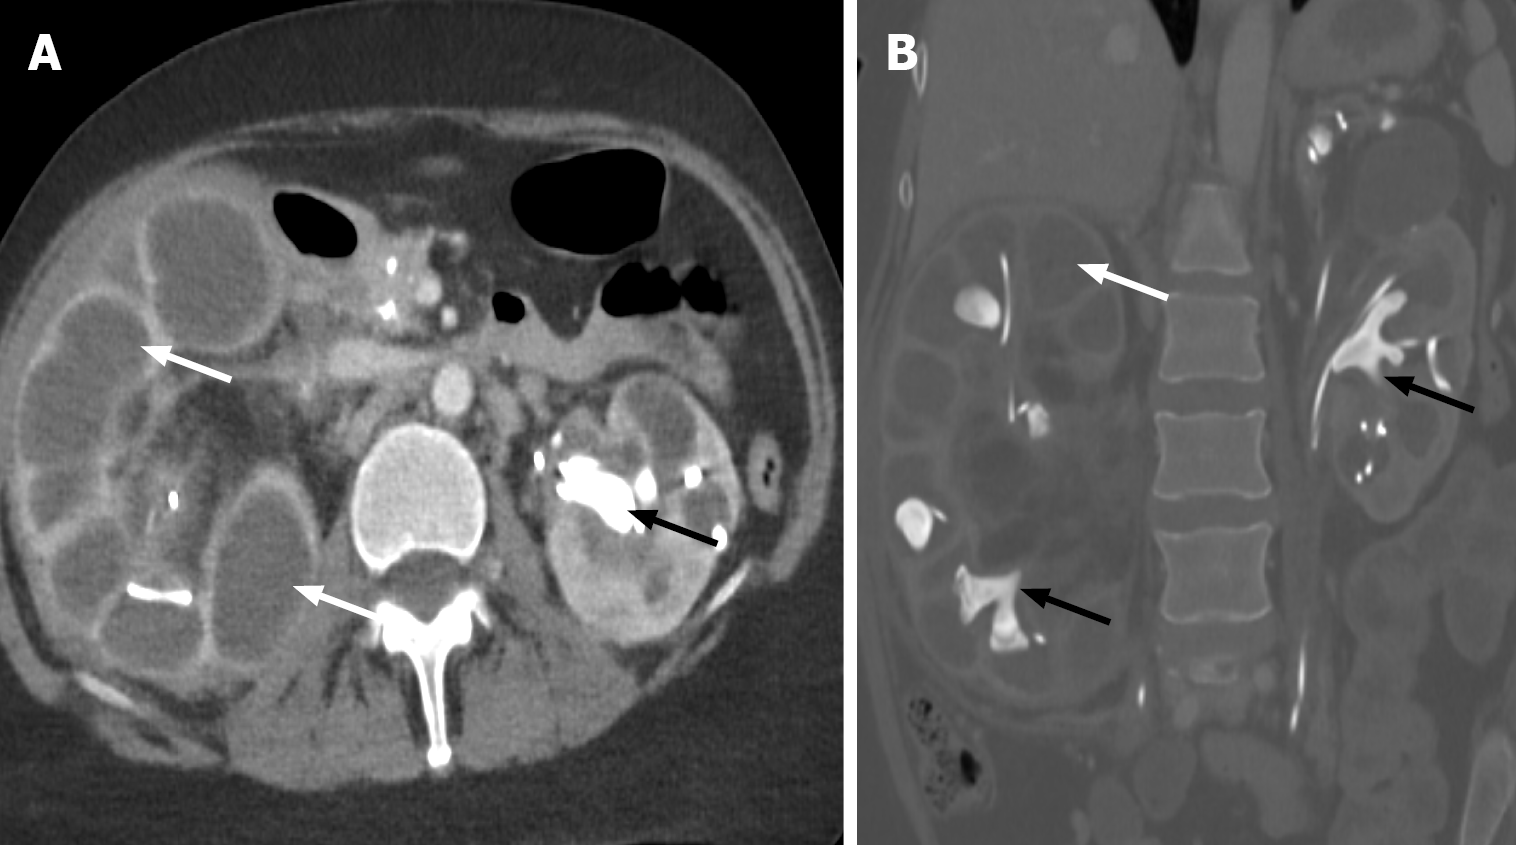

Figure 1 Grade I and II renal Injury.

A: Axial view of the non-contrast enhanced computed tomography of the right kidney demonstrates a lentiform-shaped hyperattenuating subcapsular collection (white arrow) with mass effect on the adjacent renal parenchyma (black arrow), compatible with renal subcapsular hematoma and grade I renal injury; B: Coronal view contrast-enhanced computed tomography of the right kidney demonstrates a linear hypoattenuation (white arrow) measuring > 1 cm in length, consistent with renal laceration; C: The axial view shows a slightly iso- to hyperdense perirenal collection (white arrow), consistent with a perirenal hematoma. The constellation of findings is compatible with grade II renal injury.